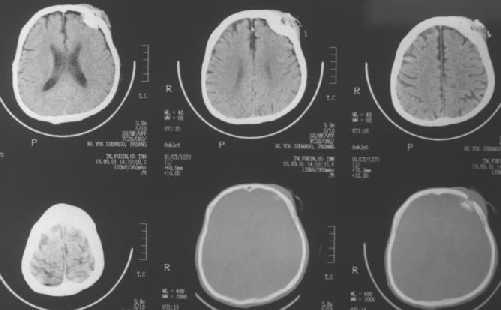

Deppressed fractures :